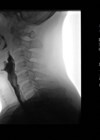

Taking life by the throat

Patients suffering with problems with their voice, airway and/or swallowing can find their symptoms immensely distressing, and their care places a huge burden on healthcare systems. We hear from a world-leading laryngologist on current and future directions. Field of interest...